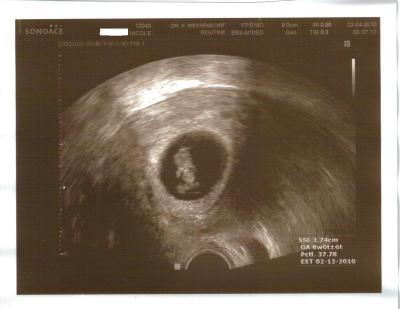

Heute endlich kann ich Euch in Ruhe berichten wie am Donnerstag der Fa Termin verlief. Zunächst einmal: ich muss immernoch liegen und habe immernoch eine Blutung und Gewebeabgänge, aber unser Flöckchen beeindruckt das überhaupt garnicht! Es wächst stur weiter wie ein Panzer auf Kurs und wir sind total stolz auf das Kleine! Ich muss nun alle 14 Tage zum Fa (zwischendrin war ich auch im Krankenhaus). Nächster Termin: 07.05. UND ich habe meinen ERSTEN MAMAPASS bekommen!!!! Das hat mir auch unendlich viel bedeutet, weil ich bei allen anderen Schwangerschaften es nie bis hierher geschafft hatte und ich auch diesmal gezittert habe, ob man ihn mir ausstellt. ET ist immernoch 30.11.2010. Die US-Fotos von Flöckchen bei 8+2 habe ich angehängt. Die Fehlgeburt droht immernoch aber ich bin wesentlich zuversichtlicher geworden und hoffe ich komme recht schnell nun in die 13 Woche. Mit Übelkeit und Kopfweh,Kreuzschmerzen muss ich mich auch im Augenblick noch herumschlagen, aber das ist peanuts. Solange es Flöckchen gut geht, ist mir alles andere völlig wurscht. Am Montag muss ich nun zur Gerinnungsambulanz und dann kann man hoffentlich was gegen die Blutung unternehmen. Mein TSH (Schilddrüse) ist wunderschön auf 1,16 gefallen und die Antikörper (Hashimoto) sind wirklich total niedrig -machen also im Moment keine Schwierigkeiten. Also kann ich alles in allem sagen: UNS GEHT ES SUPER für die Umstände. Ich möchte allen ganz lieb Danke sagen für die Daumen und alle lieben Wünsche SIE HABEN GEHHOLFEN!! BITTE WEITER DAUMEN DRÜCKEN IHR SEID MIT ZAUBERDAUMEN GESEGNET! Alles Alles Liebe Nicole / Feenstaub226

Bild zu Backup: Mein Termin vom Donnerstag - Forum für November - Mamis

FLöckchen mit Nabelschnur - ein/e echte/r Astronaut/in!